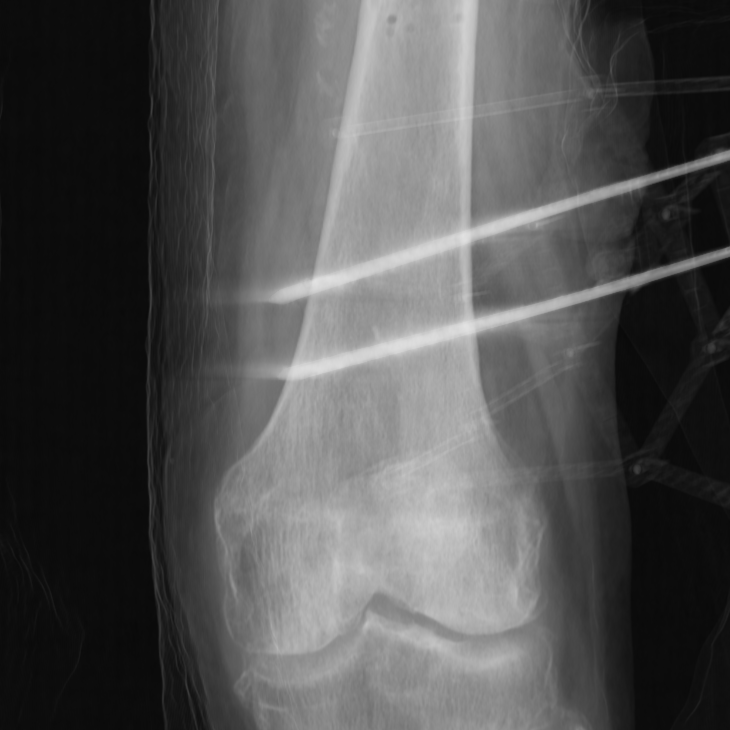

Segmenting the femur CT model into these three substructures can be performed preoperatively. However, segmenting contour pixels for each substructure intraoperatively in the X-ray images presents several challenges. The first challenge is the need for speed, as this process must be completed quickly to integrate seamlessly into standard surgical workflows. Additional challenges arise from the nature of medical imaging and the characteristics of X-ray images, such as low contrast, noise, overlapping structures, unclear or ambiguous boundaries, and artifacts. For reference, see Figure 17.

A critical step in improving the contour model predictions involved augmenting the generated DRRs at various stages to closely resemble real X-ray images. The DRRs were generated using 3D Slicer [29, 30], a robust and open-source toolbox for medical imaging. Unlike real X-ray images, which exhibit significant noise and visual artifacts (see Figure 18), the generated DRRs are typically very clean and artifact-free (see Figure 17). To bridge this gap, our data augmentation strategy focused on introducing various levels of Gaussian noise, random contrast adjustments, applying small random rotations, and simulating white edge artifacts. These standard techniques have been shown to effectively bridge the imaging domain gap between synthetic and real-world data, as supported by prior work [31]. Despite these domain gaps, our study demonstrates that our model, trained exclusively on synthetic data, generalizes exceptionally well to real X-ray images. This claim is supported by Figures 3, 4, and 5 of the main article which show results obtained on real X-ray images.